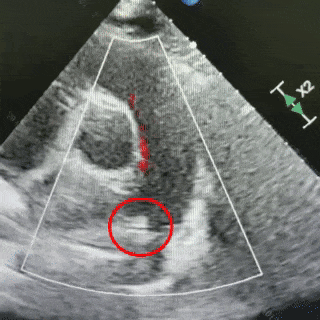

术后6个月随访

无残余分流,封堵效果良好